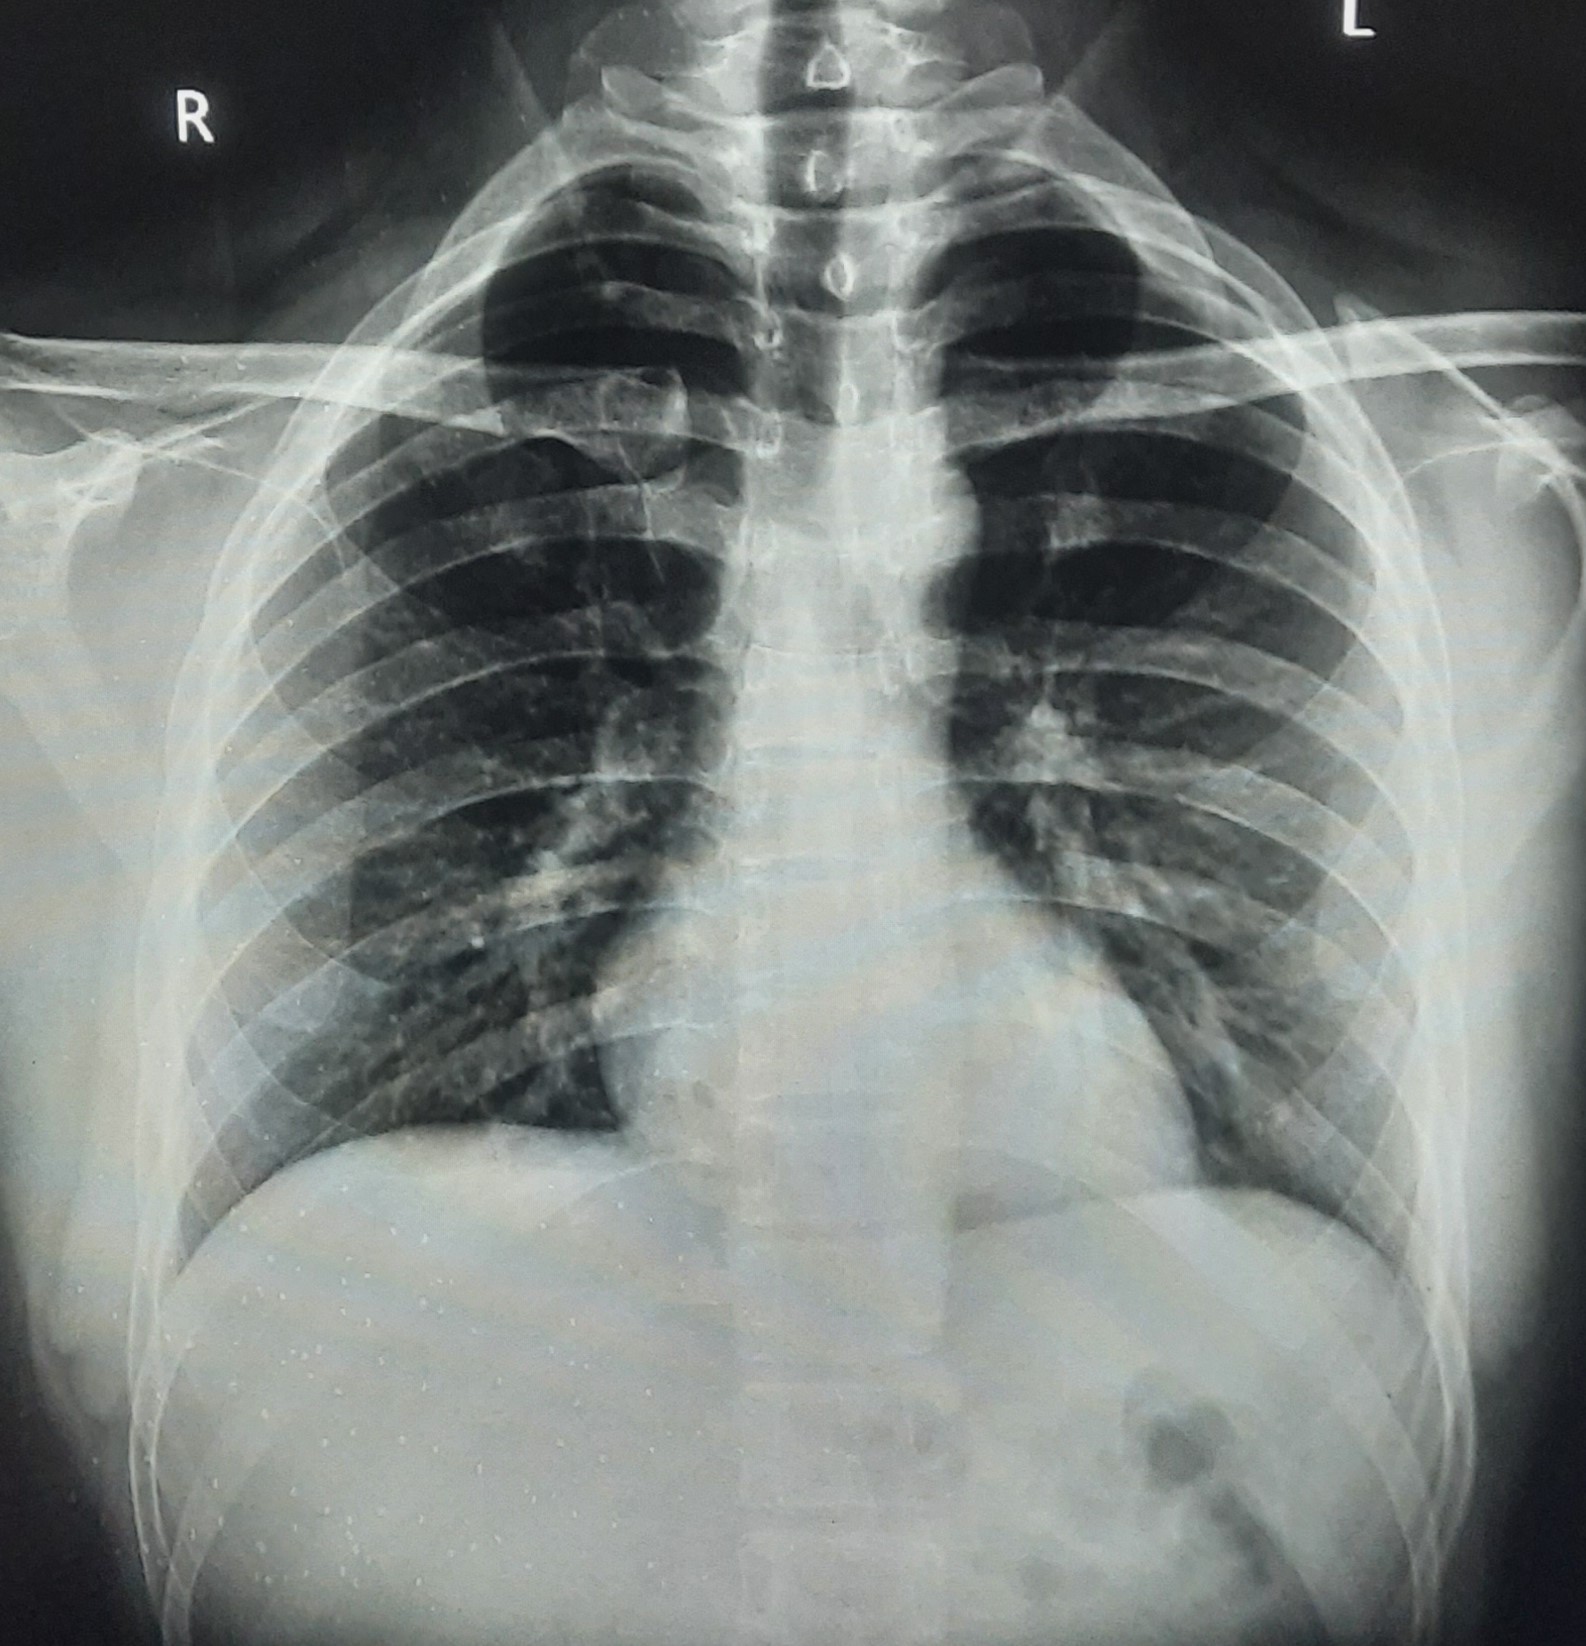

| 350 | IGGMC, Nagpur, Nagpur | P2 | 29-4122 | Pravin Thaware | Consent taken on Paper | 32 Yrs. |

Provisional Diag : Pre-Employment Medical fitness

Final Diag : CxR No Finding (Medical Fitness) |

Pure Normal Case (Cases with no complaint, NAD or medical fitness cases) | NODULAR OPACITIES SEEN IN BILATERAL HILAR REGION | No abnormality visible on x-ray |